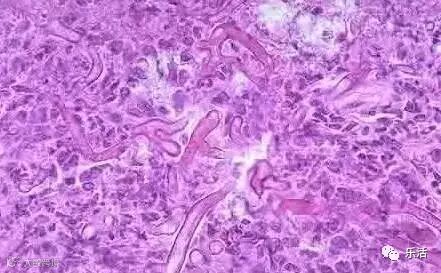

导致霉菌性阴道炎的罪魁祸首是白色念珠菌。其实在正常情况下,它也会存在于阴道中,但在自身抵抗力降低,或者念珠菌大量繁殖时,就会出现症状,比如豆腐渣样白带、外阴瘙痒等。

白色念珠菌对皮肤黏膜具有很强的黏附性及毒力,喜欢在湿润的酸性环境中生长,且它的菌丝、孢子很顽固,药物难以杀死,在机体抵抗力较强时也可在于阴道粘膜中存在,这是霉菌性阴道炎根治困难的根本原因。